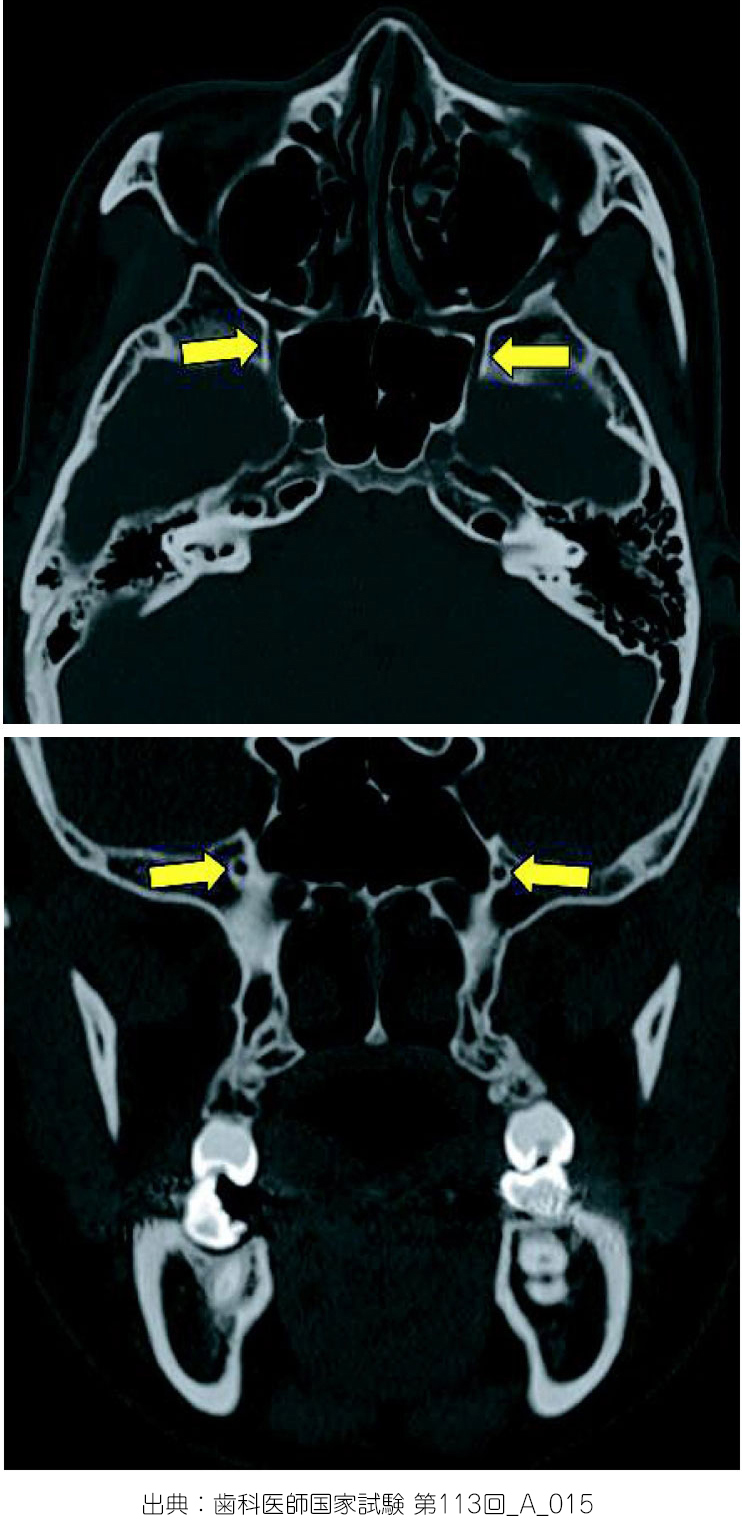

正円孔

取り急ぎ、関連画像を表示致します。なお、国家試験問題画像使用に関する権利については、厚生労働省関係部局担当者様に確認し、出典を明記することで問題ない旨を確認しております。